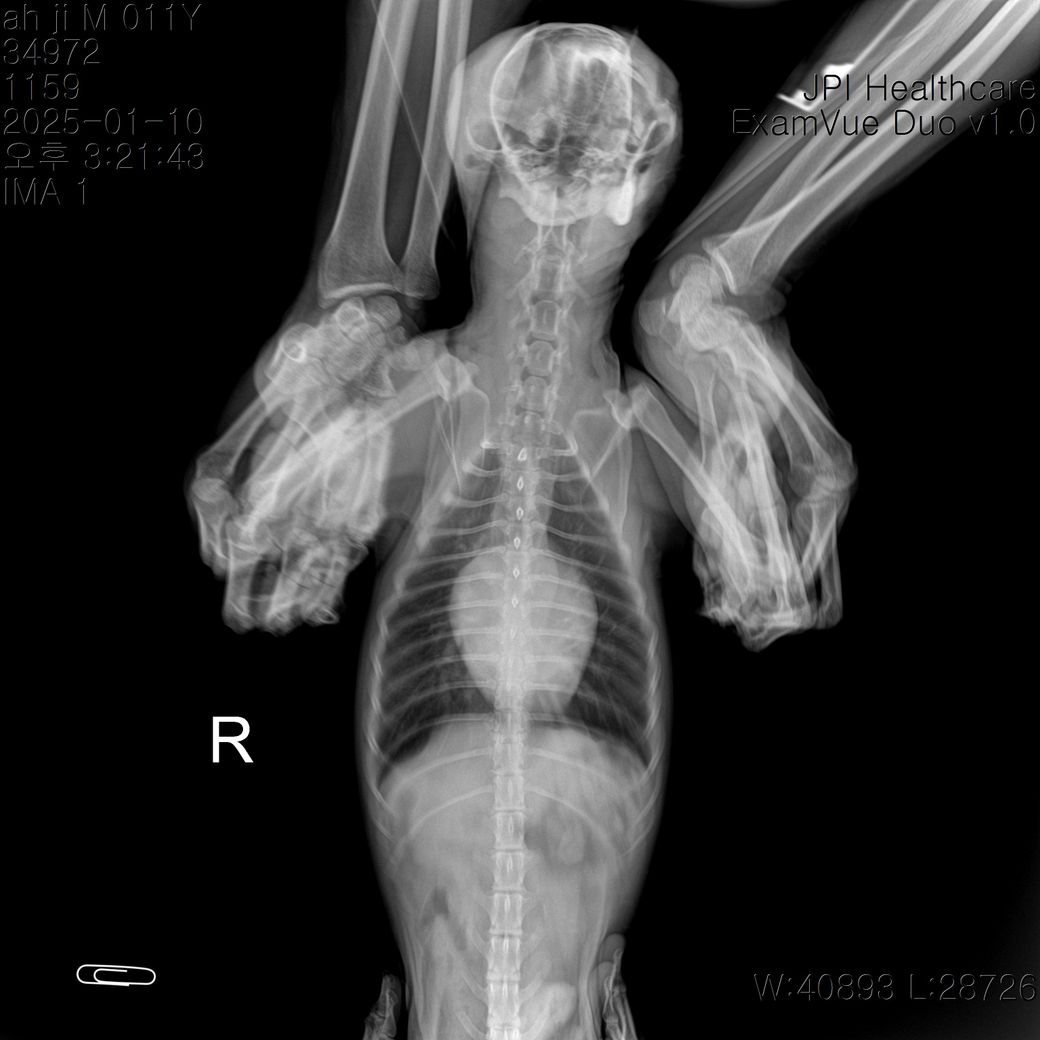

안녕하세요 심장관련 방사선 사진 봐주실 수 있나요?

안녕하세요 며칠전 방사선 촬영을 했는데요

혹시 심장비대가 관찰되는지 궁금합니다

외측상에서 심장의 크기가 늑간기준으로 4.5개로 평가되어 심한 심비대 양상이 관찰되며, 심장의 뒤쪽 허리 소실 소견과 복배상 심장의 2~3시 사이 돌출 양상, 심장의 뒤쪽 변연이 2중으로 관찰되는 양상 등 심한 좌심방 종대 양상이 관찰됩니다. 복배상 폐 후엽을 중심으로 경미한 폐 침윤 양상이 관찰되어 폐수종이 진행되고 있는것으로 보이는 바 즉각적인 처치를 하지 않을 경우 응급상황 발생 가능성이 높은 상태로 보입니다. 주치의와 상의하에 공격적인 치료 처치가 권장되는 전형적인 심장 질환 환자의 방사선 사진입니다.